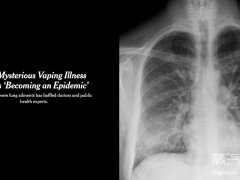

通过附上小王的肺部CT图片(如图1所示),我们可以清晰地看到他的肺部存在明显的炎症和肺气肿。这些病变使得小王的肺部功能逐渐丧失,严重影响了他的生活质量。